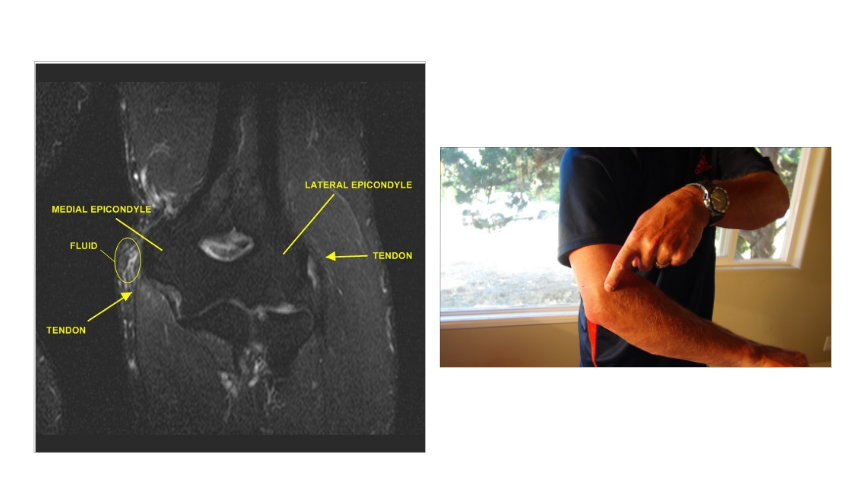

What is this?

Tennis/Golf Elbow